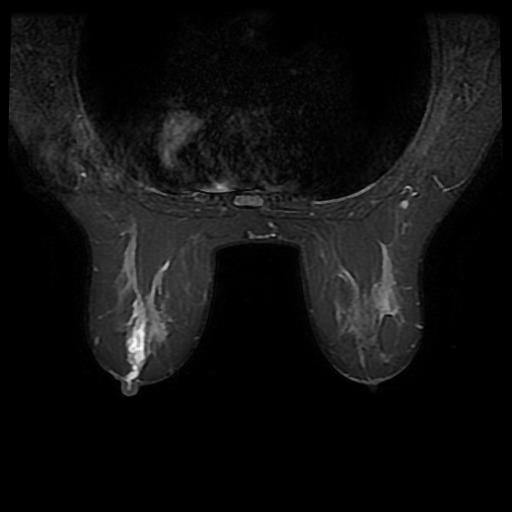

You can see radiographs and MRI images illustrating an intraductal papilloma below. Authors: Mohammad Taghi Niknejad, Bahman Rasuli. Source: Radiopaedia [11]:

5. MRI is used for clarifying diagnosis. Intraductal papillomas are characterized by the presence of a well-defined rounded mass on MRI, isointense or slightly hypointense in T1-mode, and well accumulating contrast in T2-mode.